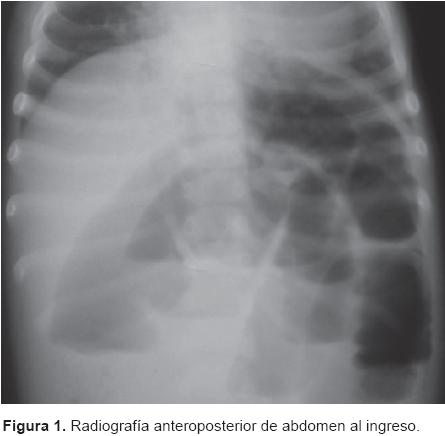

Se colocó sonda nasogástrica mostrando abundante gasto biliar. Las radiografías mostraron dilatación de asas intestinales y niveles hidroaéreos en múltiples segmentos (Figuras 1 y 2).